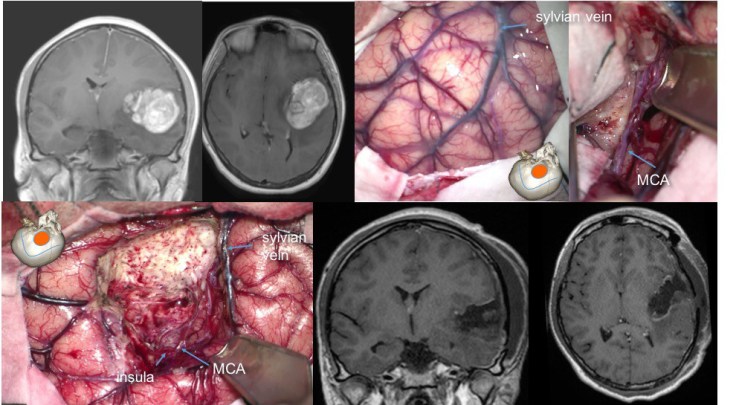

les tumeurs insulaires

elles peuvent être localisées à l’insula, ou l’envahir à partir de la région temporale ou frontale. en profondeur, elles sont en contact avec les noyaux gris centraux et la capsule interne.

- on les aborde en ouvrant la vallée sylvienne, en restant sur le versant temporal pour éviter de léser la région frontale postérieure

- les branches de la sylvienne sont séparées du cortex insulaire tumoral

- la dissection vasculaire peut entraîner un vasospasme, elle devra donc être particulièrement douce.

- il est préférable chaque fois que possible de réaliser une dissection sous-piale pour limiter la contamination de la vallée sylvienne, puis de suivre les limites tumorales.

- la partie postérieure du pédicule temporal contient les radiations optiques, et doit être respectée.

- la résection tumorale se fait par aspiration pour limiter le plus possible la dissection profonde d’avec la capsule interne et les noyaux gris.